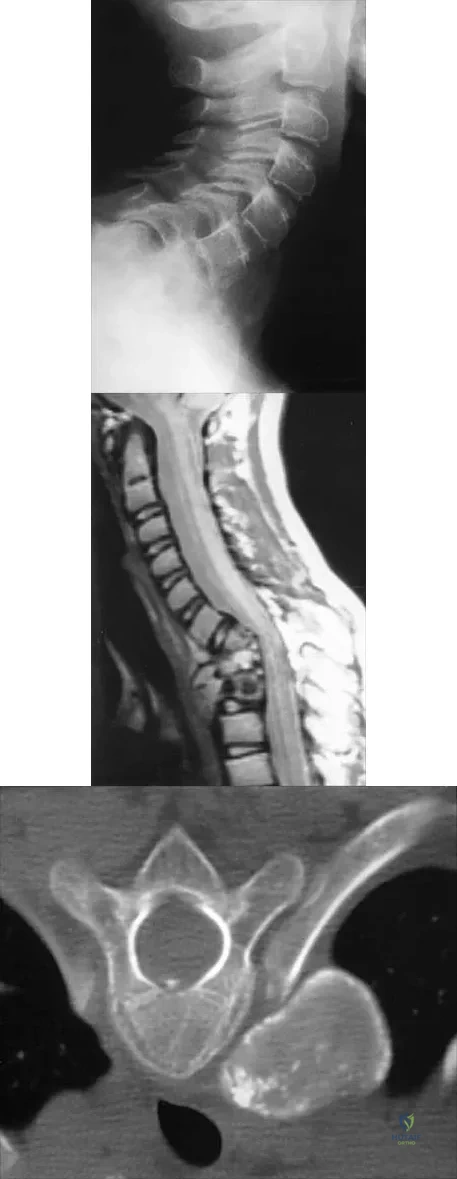

Question 66

A 53-year-old woman has severe neck and left shoulder pain after a rollover motor vehicle accident. Radiographs and a CT scan of the cervical spine are shown in Figures 34a through 34c. Management should consist of

Explanation